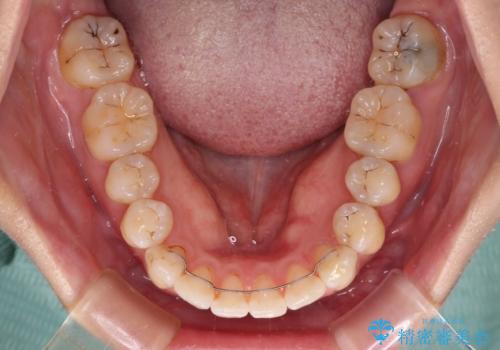

内側に転位していた歯はきれいに歯列に収まり、清掃性が著しく改善しました。

元々神経の失活してしまっている前歯2本は変色が目立つようになってきたため、今後セラミッククラウンによる補綴治療を行う予定です。